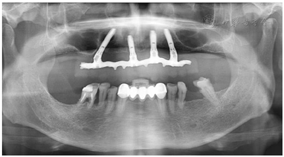

影像学检查:曲面体层片及CT检查显示11、21牙槽骨吸收至根尖1/3;12、14、17、22牙槽骨吸收超出根尖,12、22根尖圆形低密度影像,17根尖周低密度影像;18、13、23、35、45、46牙槽骨吸收至根长2/3;37近中及远中邻面可见低密度透射影像,近髓(图2)。

(1)种植一期手术:①阿替卡因肾上腺素注射液局麻下拔除上颌余留牙。②沿16-26区域牙槽嵴顶全层翻瓣,清除拔牙窝内炎性肉芽组织,平整牙槽嵴顶。③分别于12、22、25区定点,逐级备洞,12、22植入Nobel Speedy 4.0 mm×13 mm种植体;25近中倾斜植入Nobel Speedy 4.0 mm×15 mm种植体;④超声骨刀于13、14、15牙槽嵴顶8 mm处行唇、颊侧骨壁近远中向开窗,开窗面积约15 mm×8 mm,剥离上颌窦底黏膜后,15区定点,推开上颌窦底黏膜,近中倾斜备洞直达鼻底,倾斜植入Nobel speedy 4.0×18 mm种植体。⑤4颗种植体初期稳定性均达到35NCm,15颊侧骨开窗区种植体表面覆盖浓缩生长因子(Concentrated growth factor, CGF)(视频4)。⑥拔除18,12旋入RP17°3 mm复合基台,22旋入RP17°4 mm复合基台,15、25分别旋入RP 30°5 mm复合基台,修整牙龈组织,黏膜瓣复位、缝合创口,拍摄曲面体层片(图3)。

(2)即刻修复:制取上下颌硅橡胶印模,利用术前可摘局部义齿转移颌位关系,制作丙烯酸树脂临时固定义齿,咬合关系恢复至第二前磨牙,调整咬合。口内固定修复螺丝加力至15N.CM,牙龈硅橡胶封闭螺丝孔,拍摄曲面体层片(图4,图5)。